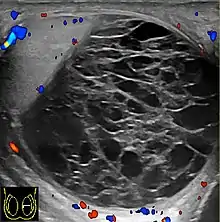

Scrotal ultrasonography of a hematocele, a couple of weeks after appearance, as a fluid volume with multiple thick septations. The hematocele displays no blood flow on Doppler ultrasonography. A pyocele has a similar appearance, but was excluded by lack of inflammation.

Hemoscrotum can follow trauma (such as a straddle injury) or can be a complication of surgery. It is often accompanied by testicular pain. It has been reported in patients with hemophilia and following catheterization of the femoral artery. If the diagnosis is not clinically evident, transillumination (with a penlight against the scrotum) will show a non-translucent fluid inside the scrotum. Ultrasound imaging may also be useful in confirming the diagnosis. In severe or non-resolving cases, surgical incision and drainage may be required. To prevent recurrence following surgical drainage, a drain may be left at the surgical site.